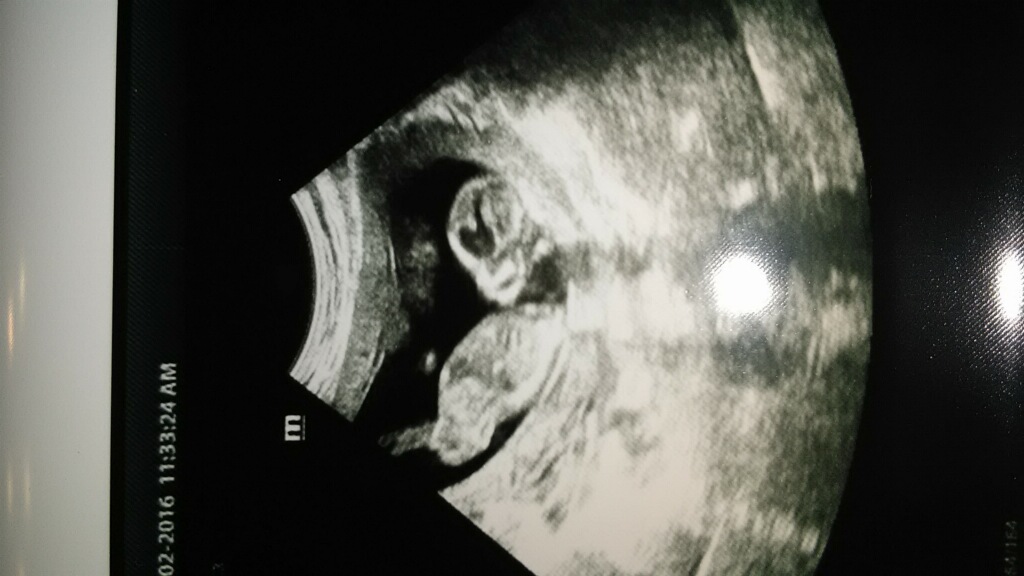

The nub looks long and flat but there is a little bulge at the end. I feel like I can't give an unbiased guess lol

I put at arrow at what I thought was a bulge. I am so excited for her! She doesn't care boy or girl.